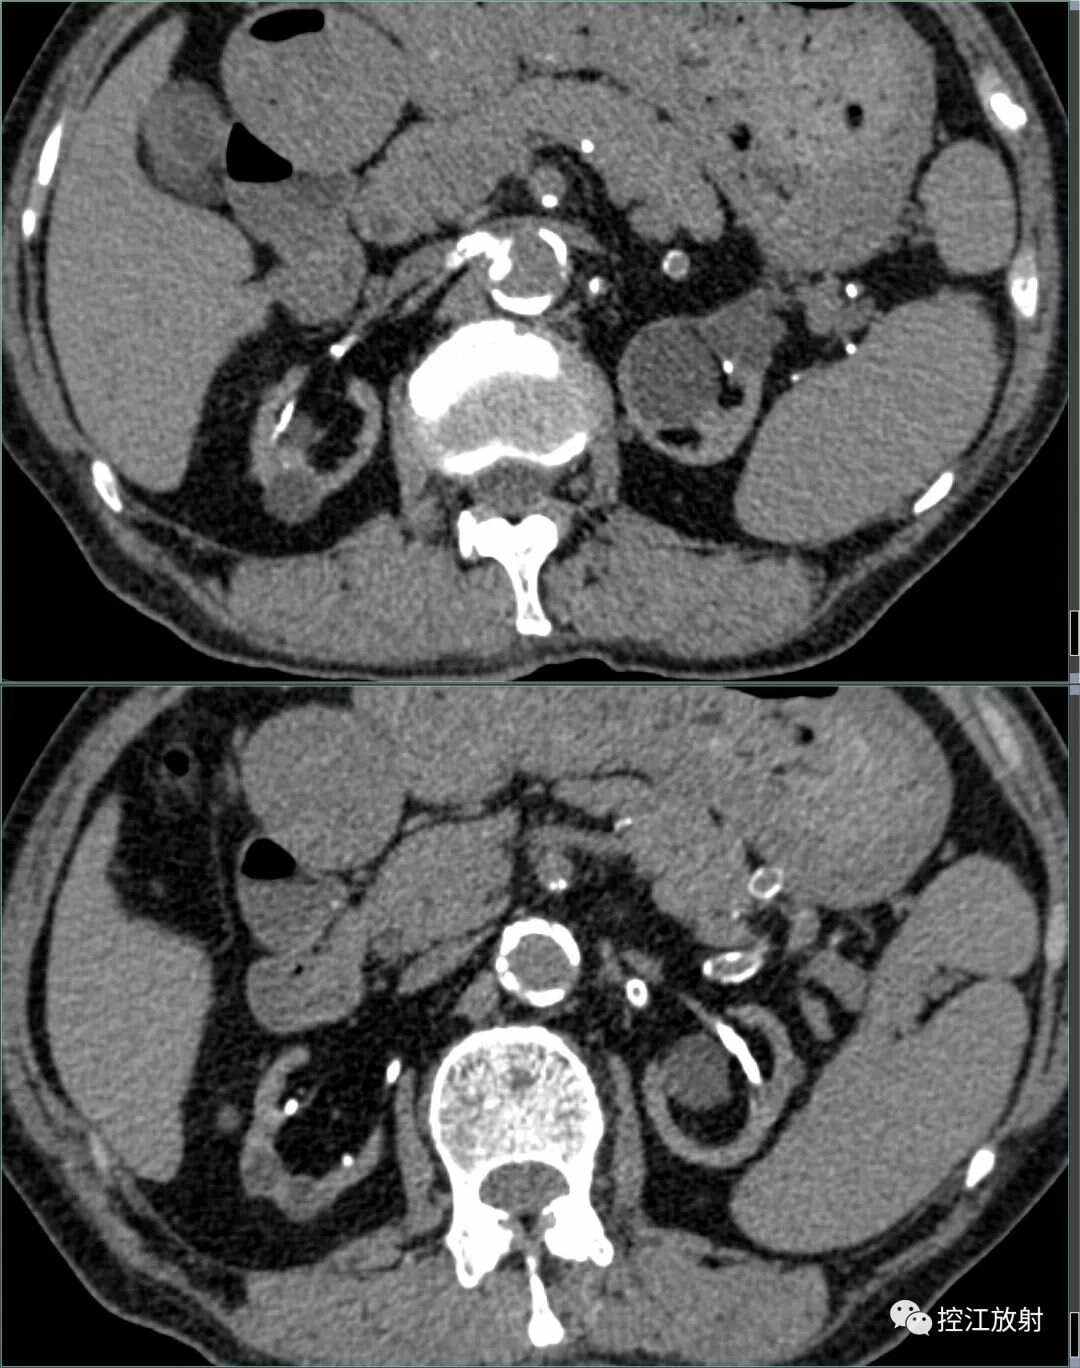

与主动脉硬化相关主动脉壁钙化通常与主动脉硬化有关,是血管壁弹性减弱脆性增强的表现动脉粥样硬化导致动脉粥样硬化是主动脉壁钙化的主要原因之一当动脉粥样硬化时间过长,就会产生钙化的斑块内膜和中膜钙化动脉钙化分为内膜钙化和中膜钙化内膜钙化与粥样硬化有一定关系,而中膜钙化则可能。

主动脉壁钙化是指主动脉血管壁出现钙质沉积的现象以下是关于主动脉壁钙化的详细解释形成原因动脉硬化是主动脉壁钙化的主要原因之一,由于动脉壁内脂质沉积和纤维组织增生,导致血管壁逐渐失去弹性不良生活习惯如吸烟饮酒缺乏运动等,这些因素会加速动脉硬化的进程长期血压升高高血压是导致;主动脉钙化是指在主动脉内壁上出现钙盐沉积,导致血管变硬变窄的病变,通常需要视情况进行治疗以下是关于主动脉钙化的详细解答一主动脉钙化的定义 主动脉钙化是主动脉内壁钙盐沉积的一种病变,会使血管变硬变窄二主动脉钙化的检查与诊断 通常通过X光超声等检查方式来诊断主动脉钙化三。

成因这通常是动脉粥样硬化发展的结果,即动脉壁上的脂肪和钙质沉积逐渐增多,形成斑块病理变化钙化斑块主动脉壁和冠状动脉壁上出现钙化斑块,这些斑块可能导致管腔狭窄或闭塞管腔狭窄冠状动脉狭窄时,会引起心肌缺血,进而出现心绞痛心律失常,甚至心梗的情况动脉瘤或夹层在主动脉钙化的情况。